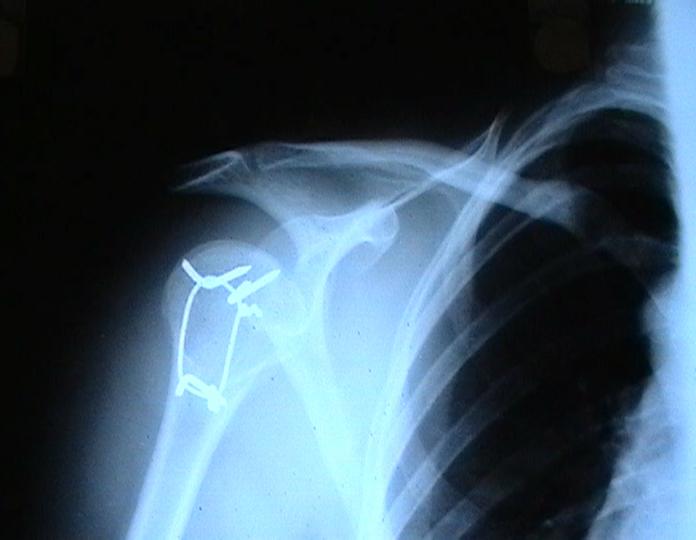

Мужчина 25 лет 16 августа 2002 г. в автоаварии получил перелом шейки плеча (снимок 1); 5 сентября в городской больнице выполнен остеосинтез пластинкой (снимок 2).К настоящему времени попал к нам на разработку ввиду выраженной контрактуры плечевого сустава. В течение последнего месяца беспокоят умеренные боли в области плечевого сустава, усиливающиеся при разработке, еще и торчит край пластинки. Нынешняя рентгенологическаякартина на снимках 3 и 4. Головка плеча уменьшается, сращение сомнительное.Кроме удаления пластинки, что еще на сегодня целесообразно сделать?Заранее спасибо.

Согласен с вашим мнением -асептический некроз головки плеча. Есть ли у вас надежды на реваскуляризацию головки ? Если надеетесь, то имеет смысл продолжать физио, если нет, то следует думать опротезировании.

I think the AVN is at least stage 3 with deformity of the head. I would advise a removal of implant and a cementless humeral head replacement. Or if you have the experience and the implant, as well as adequate bone stock, maybe a resurfacing prosthesis like the Copeland shoulder. I am not sure if you can do it one or two stages. You can perhaps do it in one stage if there is no sign of infection and if the patient condition allows it. You should not worry too much about age since this is a non

The current xrays indicate failure of the implant with losening. I would make sure there was no evidence of infection ( exam,ESR,CRP etc.) . I would agree with implant removal . I think this would be a suitable case for a circular ring fixator and compression, either a standard IIizarov or Taylor Spatial frame would be appropriate. I note from your previous cases that you have a high level of experience with this method.